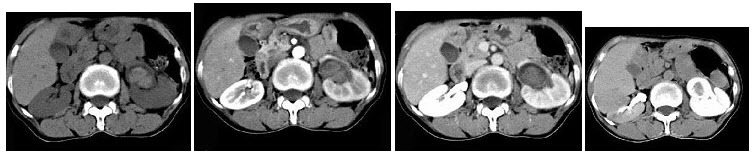

男,5岁,消瘦、贫血、纳差和腹部包块3月余,CT检查如图,下列说法正确的是()

A.右侧腹腔内可见一巨大软组织肿块影,其边界欠清楚

B.肿块密度不均匀,可见片状的较高密度,考虑为出血,也可见点状的钙化影

C.该病灶来源于肝脏,考虑为肝母细胞瘤

D.该病灶来源于右肾上腺,考虑为神经母细胞瘤

E.该病灶来源于右肾,考虑为肾胚胎瘤